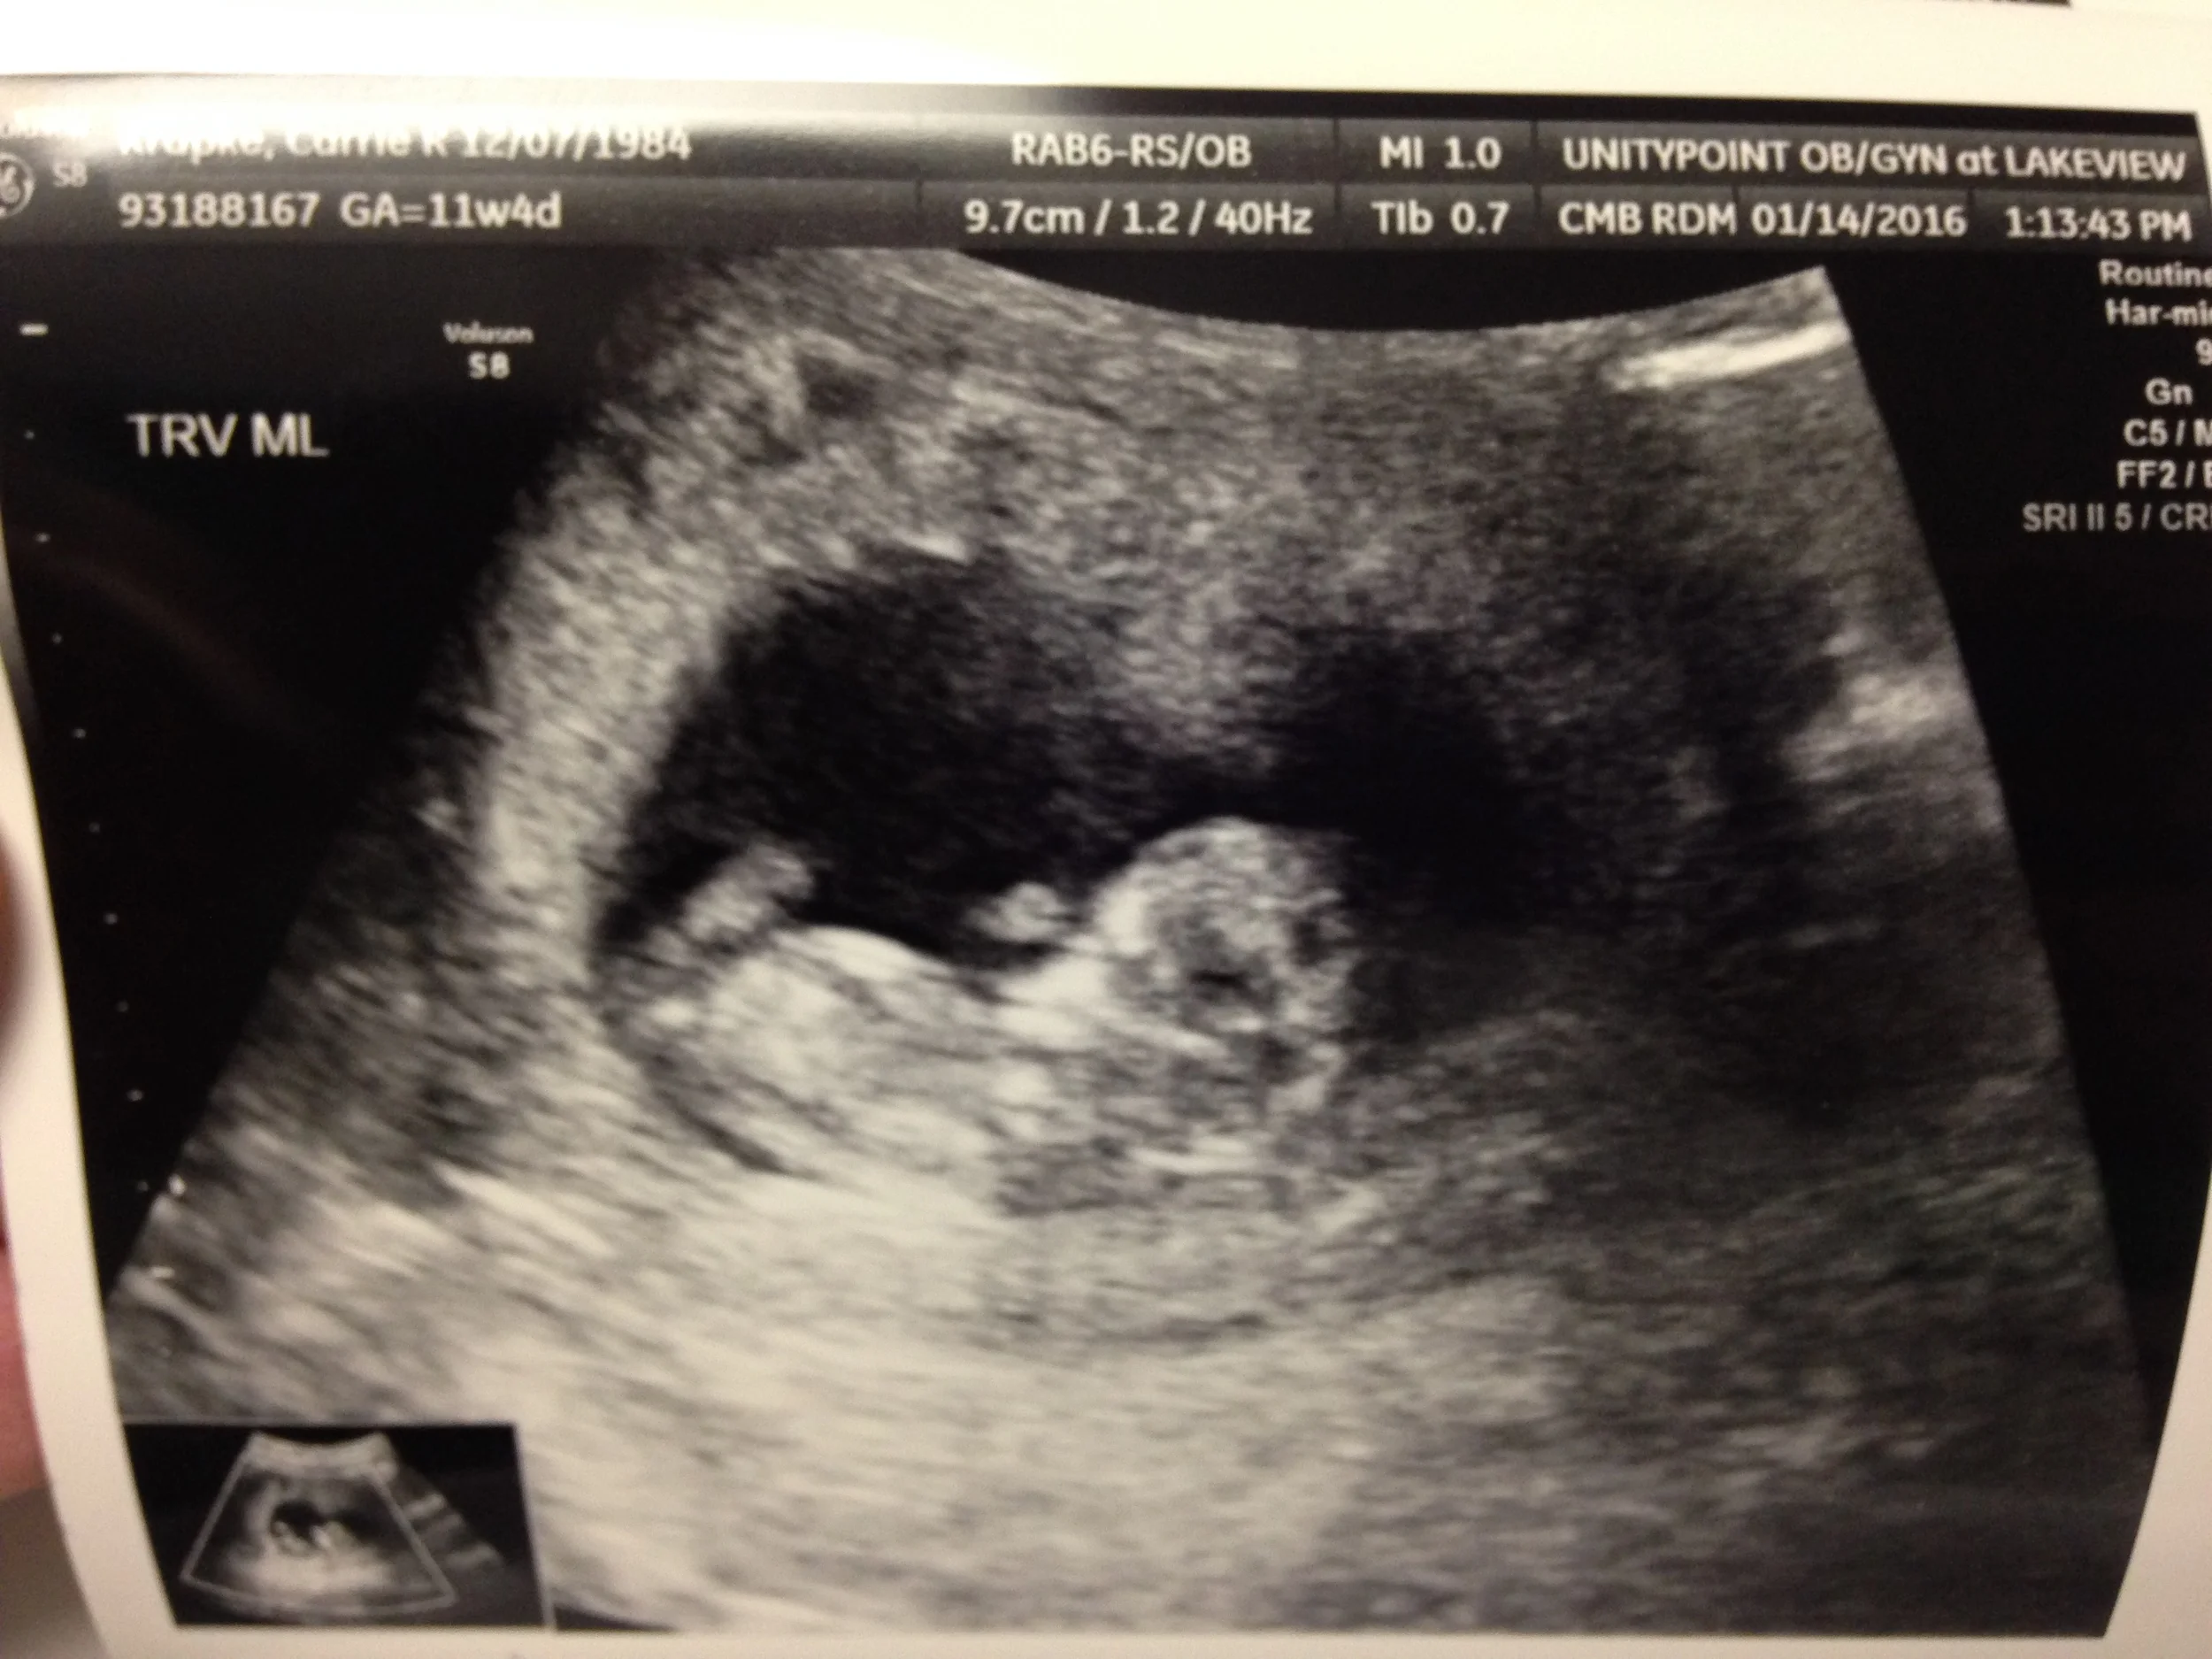

Being considered a smidge higher risk than a normal pregnancy has its perks. We’ve seen this peanut a whopping 5 times via ultrasound already and each one had me holding my breath, clenching my jaw with tear-filled eyes closed, praying for the tech to turn the screen towards me so we could see the flickering of its heart. It’s been incredible to watch a gathering of cells at a mere 5 1/2 weeks, the size of a piece of rice, grow and develop to have a human profile.

Once we’d had our 5th ultrasound at 11 weeks with Baby #4, I made the second heart out of the memorial’s rose petals and framed it. They now both rest on our bedroom wall under Adelaide’s newborn photo and a photo of Gerard and I.